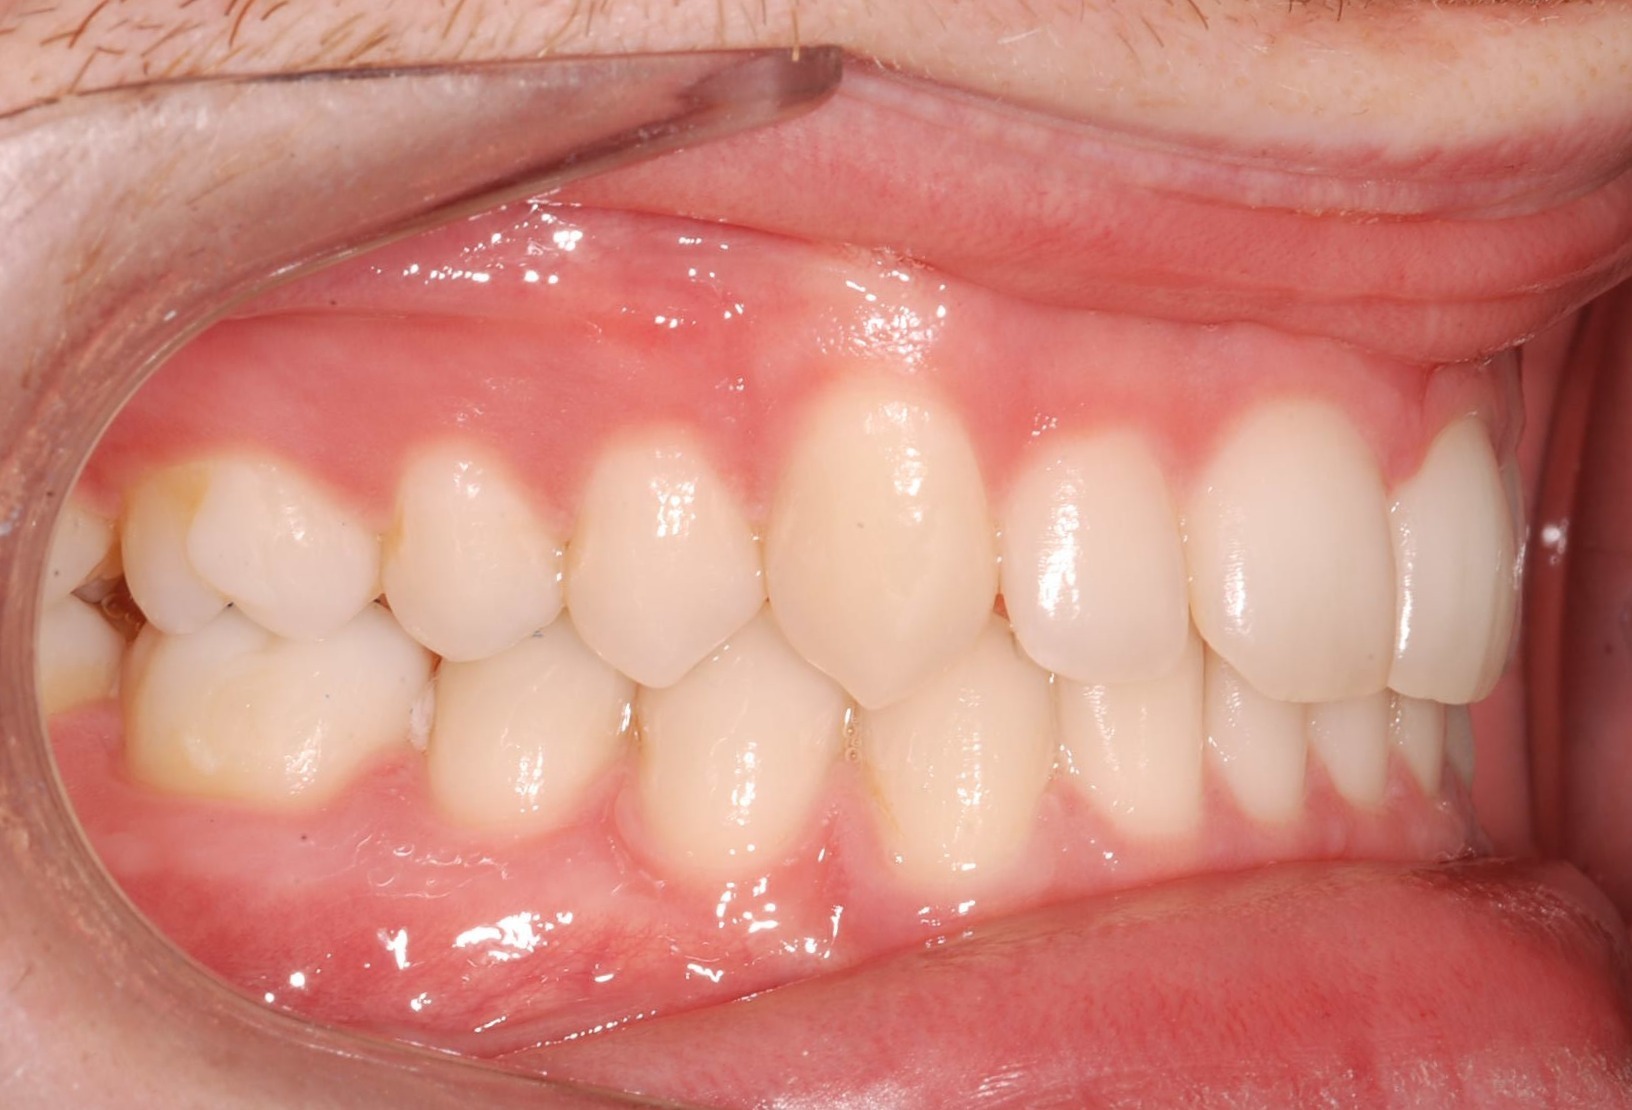

Class II subdivision malocclusions can be difficult to treat because of their asymmetric occlusal relationships. An accurate diagnosis, etiologically based when possible, is essential to perform a correct and efficient orthodontic treatment.

The aim of this article is to illustrate a case report treated with customized lingual brackets in association with a simple vestibular device.